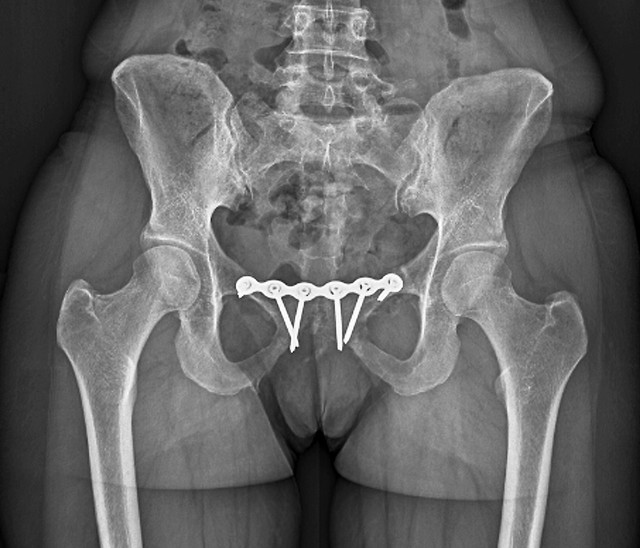

如果你出现了假胯宽,怀疑自己存在耻骨联合分离,可以通过到医院拍片来检查判定。

宝妈容易出现假胯宽,其中很多人都存在轻度的耻骨联合分离。有的会出现骨盆失稳,臀部扁、平、宽,小腹突出,*处私**松弛,甚至会出现尿*禁失**,如果没有明显的不适,一般通过矫正锻练都可恢复。

如果严重的话,往往还可能伴随着耻骨痛,大腿根疼,特别是侧身睡觉和负重的时候,疼痛感会更加明显,会影响正常的行走。有的还会出现持续的腹直肌分离。如果你这些症状,建议去医院接受治疗。

耻骨联合分离也是很多宝妈在产后恢复时,减重成功,但穿之前的裤子仍然太瘦的原因。